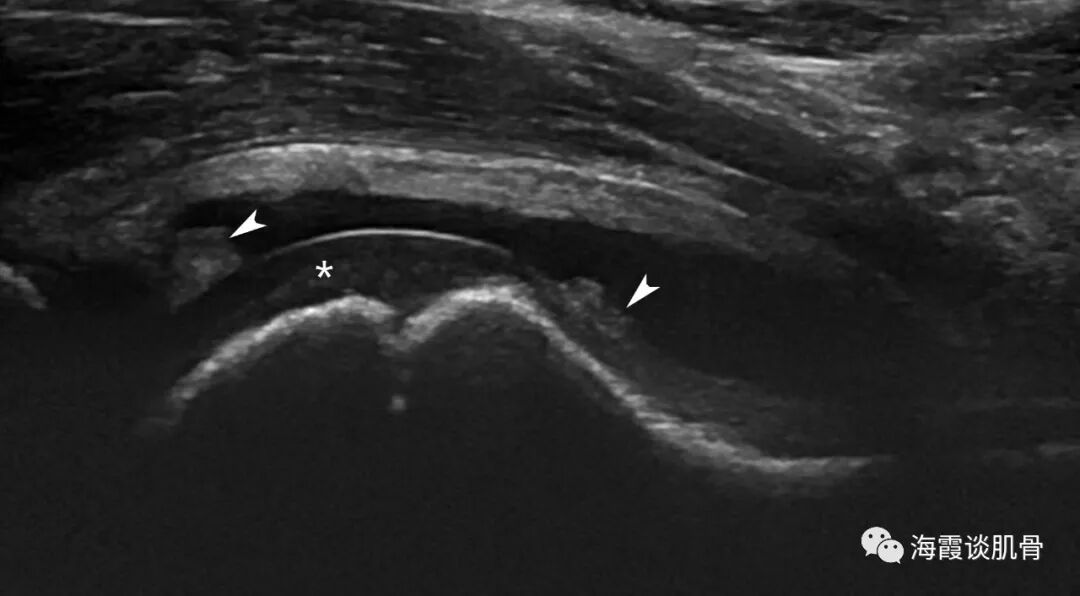

病例2 女,6岁,突发右膝关节疼痛,并跛行,扫查右膝关节未发现异常声像,随检查右髋关节。

图四: 右髋关节关节囊扩张,除积液外可探及少许滑膜增生(箭),*为关节软骨